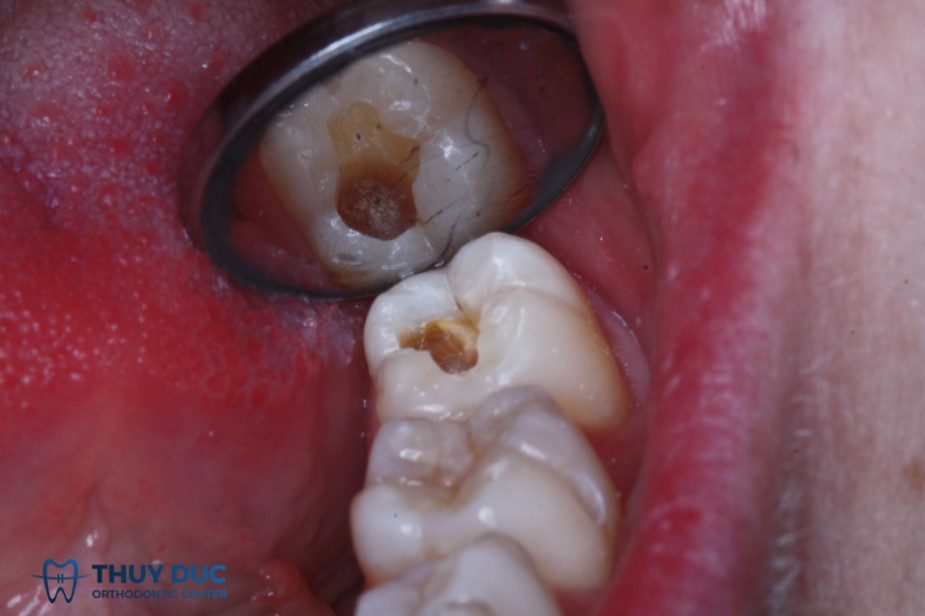

1) Đánh giá mức độ sâu răng

- Trám chỉ phù hợp khi răng đã tạo lỗ nhưng chưa vào tủy.

- Nếu chỉ mới sâu chớm (đốm trắng), thường không cần trám, chỉ cần fluoride.

- Nếu răng sâu quá lớn hoặc đau dữ dội, trám không còn hiệu quả.

2 Các bước thực hiện trám răng

- Vệ sinh răng miệng: Làm sạch răng, loại bỏ mảng bám trước khi trám.

- Gây tê (nếu cần): Một số trẻ sẽ được gây tê cục bộ để giảm đau.

- Loại bỏ mô răng bị sâu: Nha sĩ dùng máy khoan hoặc dụng cụ chuyên dụng để loại bỏ phần răng mục.

- Làm sạch và chuẩn bị hố răng: Loại bỏ vi khuẩn, làm khô bề mặt răng.